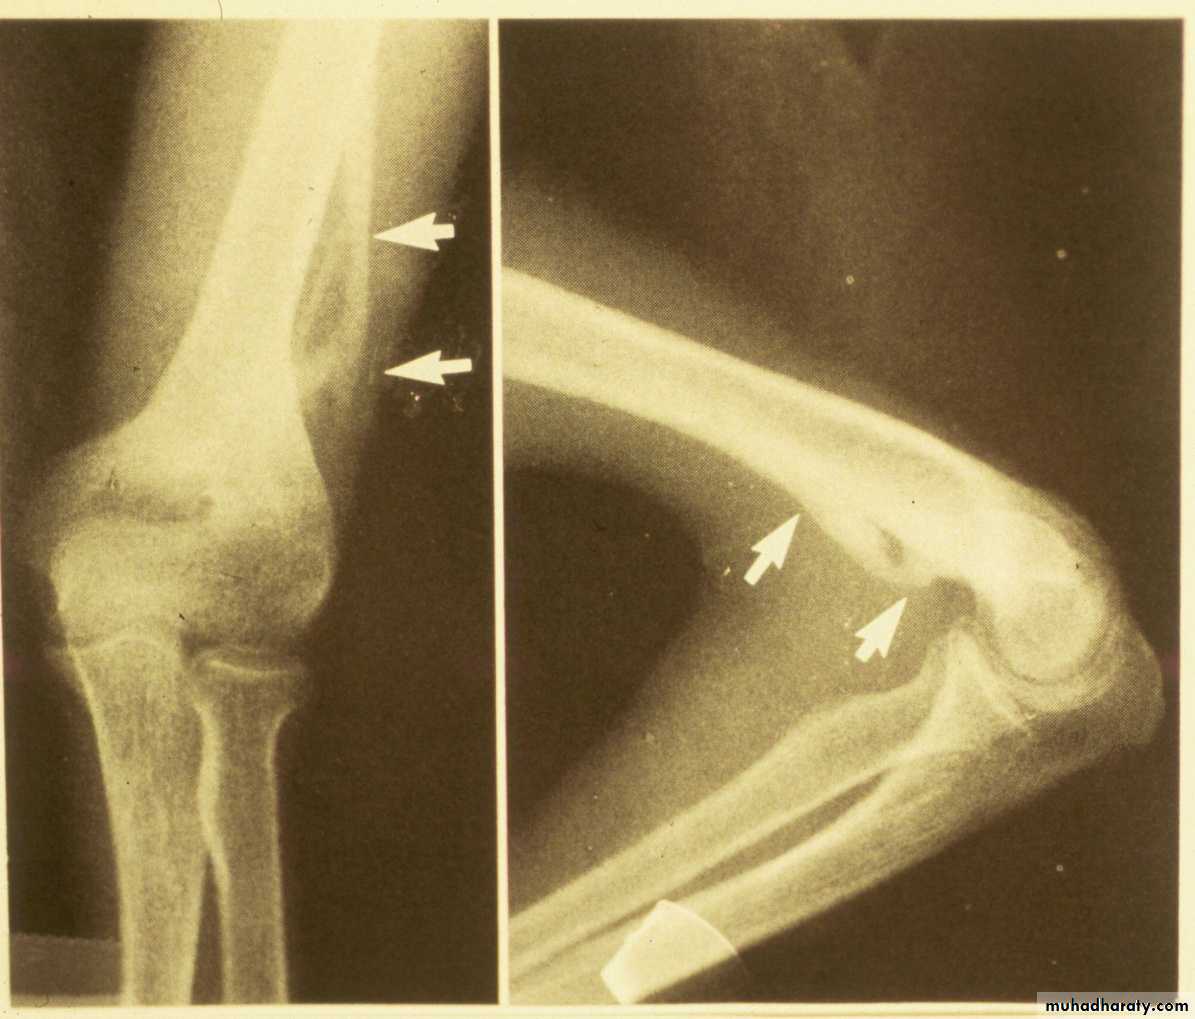

If there was no definite fracture

seen on the injury films,what confirms the presence

of a suspected Type I fracture?

Injury film

3 wks post fracture

fat pads displaced

Type I suspectedPeriosteal new bone

The original suspicions of

a fracture are now confirmed.